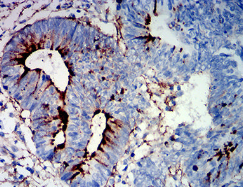

IHC    1/200-1/1000